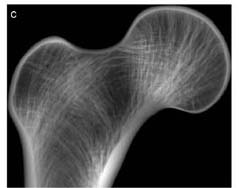

The mesh and the loading on a head of the femur (far left).  The analysis confirmed that the Principal Stresses (middle images) predicted by the analysis corresponded to the trabecular growth patterns (far right). These growth patterns can be seen in the CT image to the right. The von Mises Stress distribution can be seen in the image below.